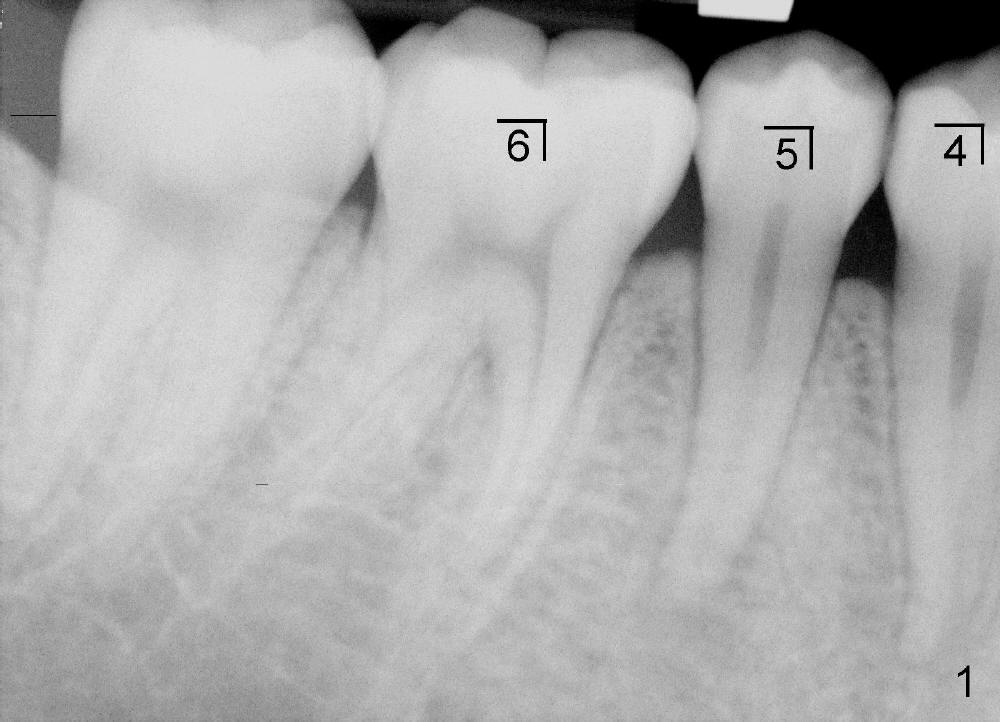

十八岁中国男孩下周一来诊所做右下五根管治疗,他妈妈转来X光片(图一),它有什么特点?不妨也分析邻牙(右下四,六)牙根形态。